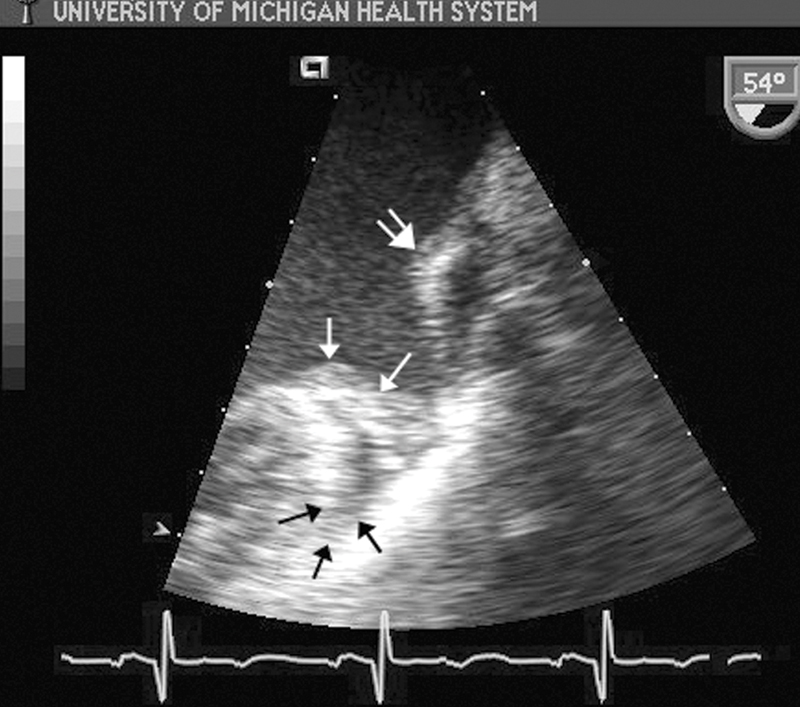

فحوصات تشخيصية لبعض امراض القلب والشرايين التاجية